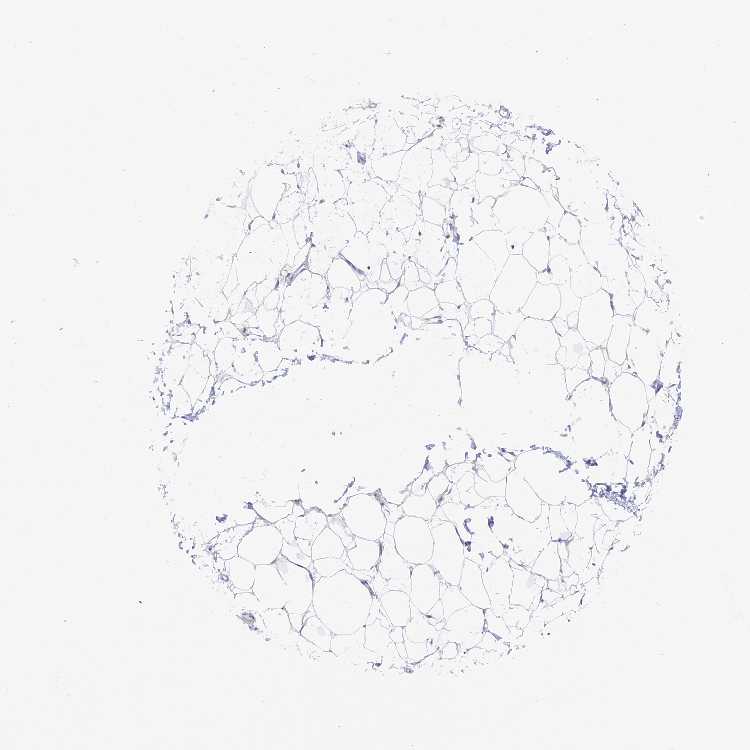

SOFT TISSUE 1 - Antibody stainingi

Antibody staining in the annotated cell types in the current human tissue is reported as not detected, low, medium, or high, based on conventional immunohistochemistry profiling in selected tissues. This score is based on the combination of the staining intensity and fraction of stained cells.

Each image is clickable and will lead to virtual microscopy that enables deeper exploration of all samples and also displays staining intensity scores, fraction scores and subcellular localization as well as patient and tissue information for each sample.

Antibody HPA043053

Chondrocytes Not detected

Fibroblasts Not detected

Peripheral nerve Not detected